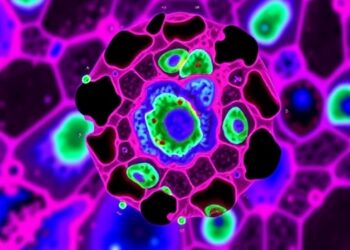

Scientists Create a Minimally Invasive, More Accurate Technique to Evaluate Immunotherapy Success

Immunotherapy has revolutionized the landscape of cancer treatment, transforming previously incurable malignancies into potentially manageable diseases by harnessing the patient’s ...